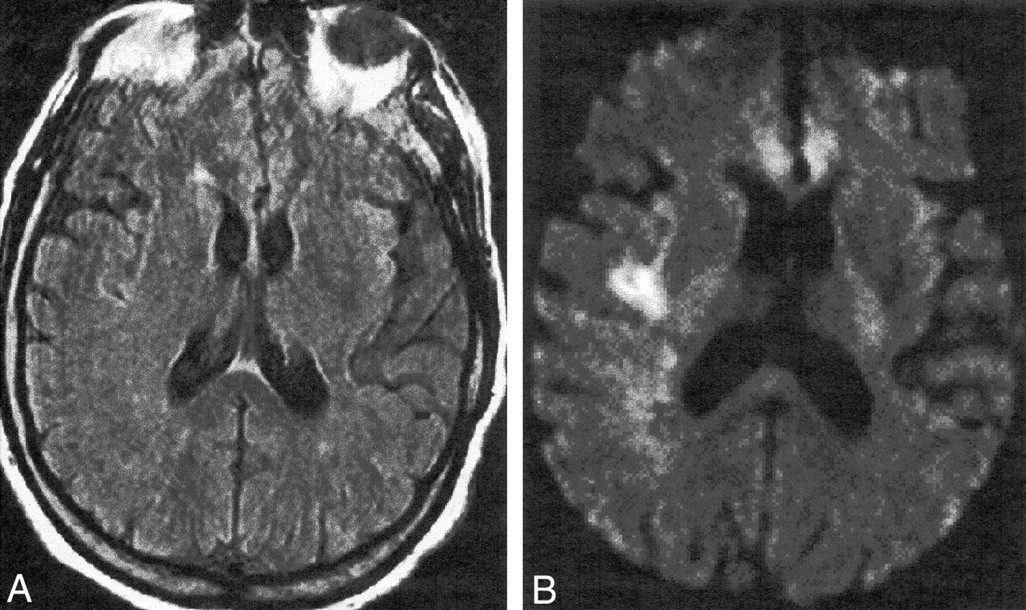

Иллюстрации и пояснения: гиподенсивный очаг на КТ головного мозга